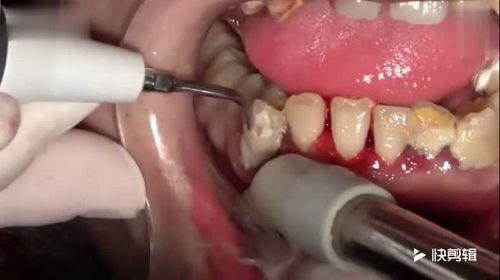

洗牙石的话音刚落,屏幕上立刻出现了一系列搞笑的画面。原来,这块洗牙石见证了无数患者的牙科治疗过程,从拔牙到补牙,从洗牙到镶牙,它都一一记录在案。

“你们看,这是我最近见证的一次拔牙手术,医生的技术真是高超啊!”洗牙石自豪地展示着一张照片。